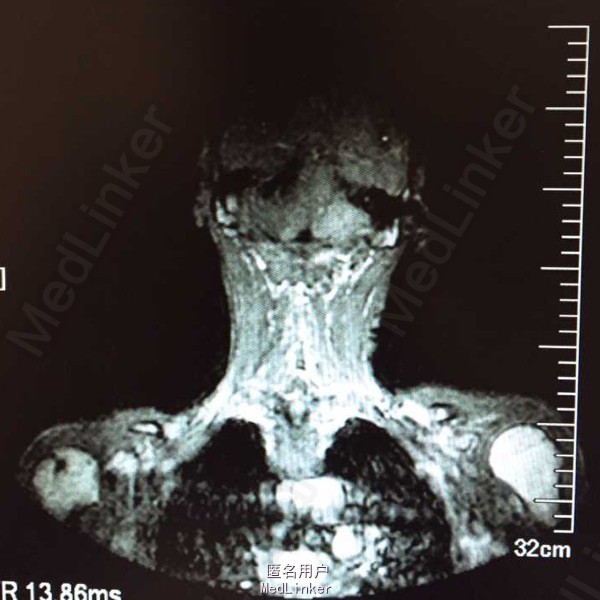

男,车祸致全身瘫痪2天,头面部,腰背部,腹部等全身各处疼痛,无昏迷

行颅脑及胸、腹部CT提示:硬膜下积液可能、肋骨骨折,胸11-腰1压缩性骨折,L3右侧横突骨折,给予对症治疗后转入我院,行CT检查提示:双侧胸腔积液,双侧腹肌肌间隙内积液,给予止痛、营养神经。行腹部CT:1.肝右后叶点状钙化:胰管轻度扩张;前列腺增大并钙化。2.双侧胸腔积液;双侧腹肌肌间隙内积液(左侧显著)3.胸11、12、腰1椎体压缩性骨折;右侧下位肋骨多发骨折;腰3、4横突骨折。

初步诊断:1胸11、12、腰1椎体压缩性骨折2.腰3、4横突骨折;3.闭合性胸部损伤:双侧胸腔积液、多发肋骨骨折。